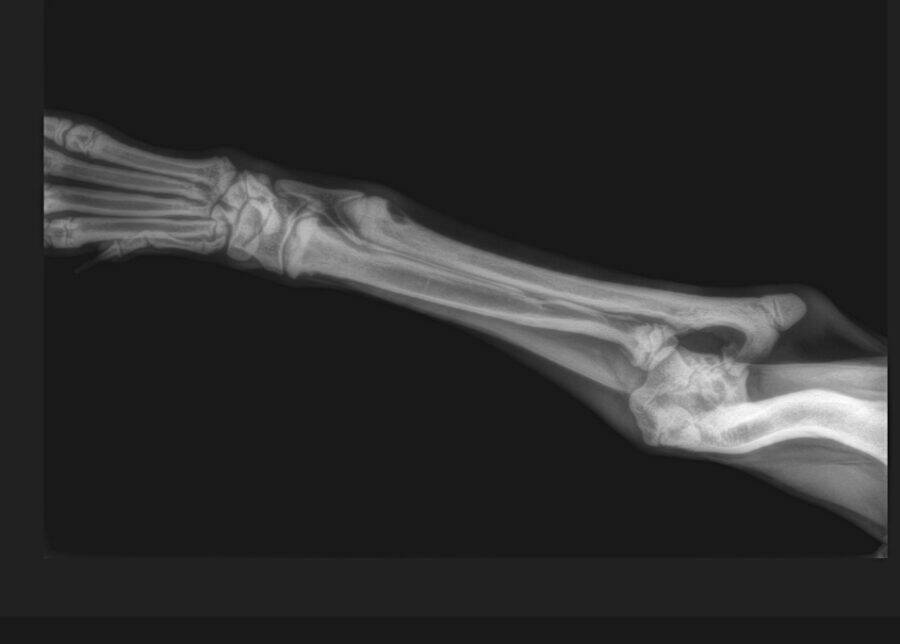

Der kleine Mickey war erst ca. 4 Wochen alt und musste in seinem kurzen Leben schon viel aushalten. Seine Rute wurde abgeschnitten und sein Vorderbein war ausgerenkt. Wir waren deshalb direkt bei unserem Knochenspezialisten, der versucht hat, das kleine Beinchen wieder einzurenken. Leider hat dies nicht geklappt und Mickey bekommt aktuell Physiotherapie.

Eine erneute Untersuchung und Röntgen im Juni 2022 haben gezeigt, dass seine Knochen im Vorderbein so verdreht sind, dass eine Operation nicht erfolgversprechend ist. Aktuell kann Mickey mit seinem Handicap schmerzfrei und mit wenigen Einschränkungen gut leben. Er bekommt zusätzliche Vitamine aber es ist möglich, dass sich sein Ellbogengelenk mit zunehmendem Gewicht entzündet und eine Amputation des Beines notwendig wird.